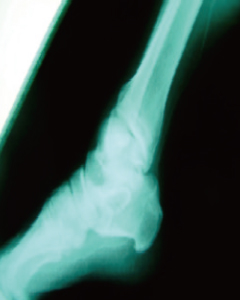

골다공증

Osteoporosis-

Before

-

BMD 0.5601g/cm² BMD 0.5918g/cm²

After

골다공증의 경우 줄기세포 치료로 골밀도가 현저하게 증가 되었음을 볼 수 있습니다.